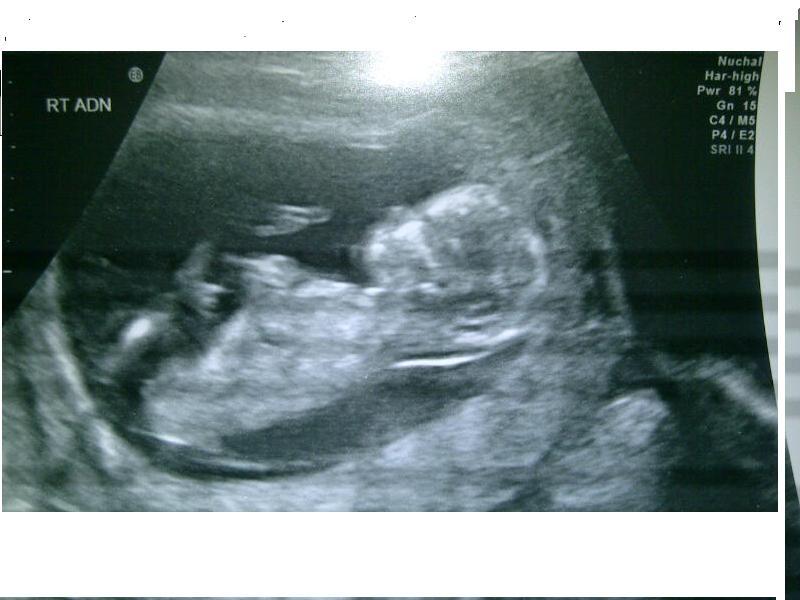

I'd really appreciate your guesses. The scan was taken at 12w 6d. Many thanks

Boy nub and skull. Not the flattest spine, but I'd still say boy!

Slight boy lean, not sure what I am seeing is nub :)